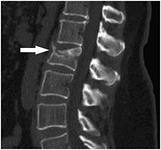

- Итог таков - у братика компрессионный перелом позвоночника, - пояснила Альбина. - Сейчас он находится в хирургическом отделении детской больницы в медгородке. Ходить ему можно по минимуму, сидеть нельзя вообще. Врачи пока ничего не говорят, но скорее всего, нужно будет заказывать корсет.